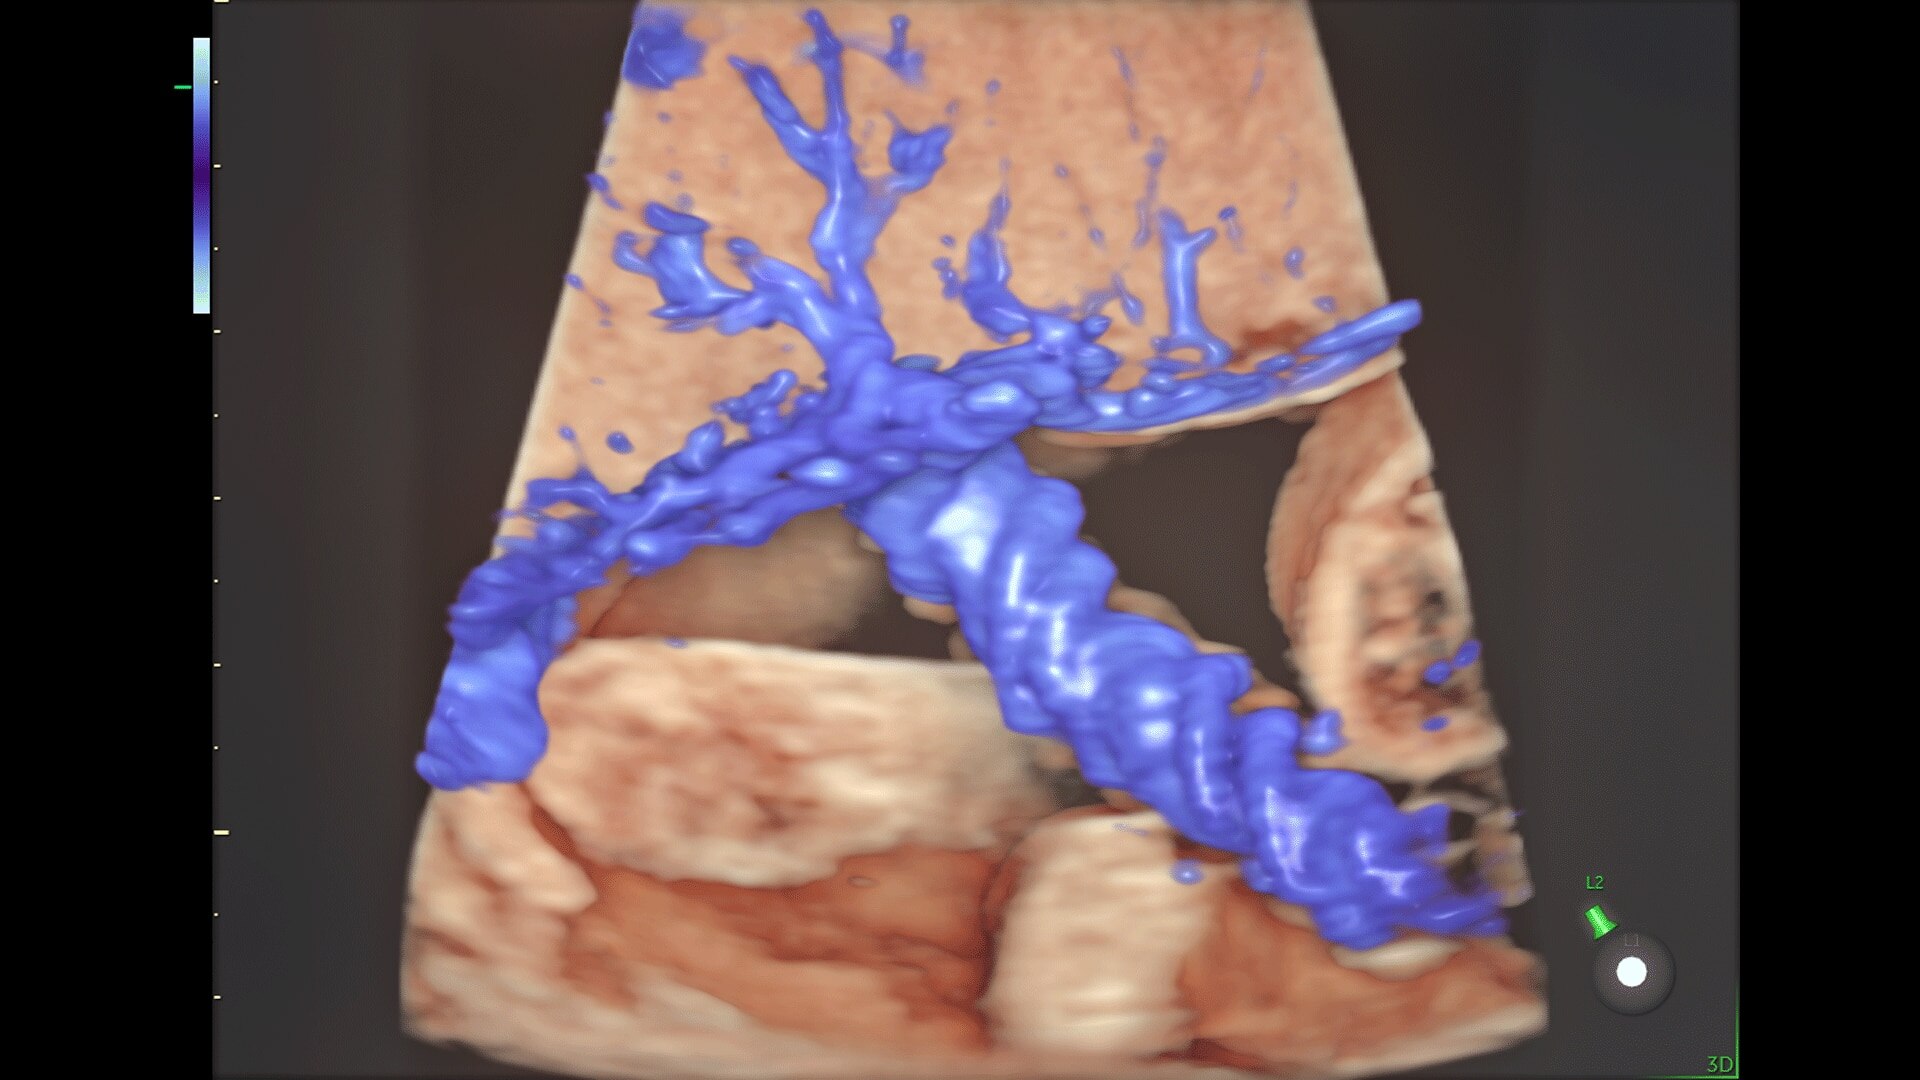

Generate spectacular 2D/3D and color Doppler images with increased penetration and stunning clarity, to help visualize critical details needed for diagnostic assurance. The Lyric Architecture unlocks new imaging and processing power to expand your imaging capabilities for years to come